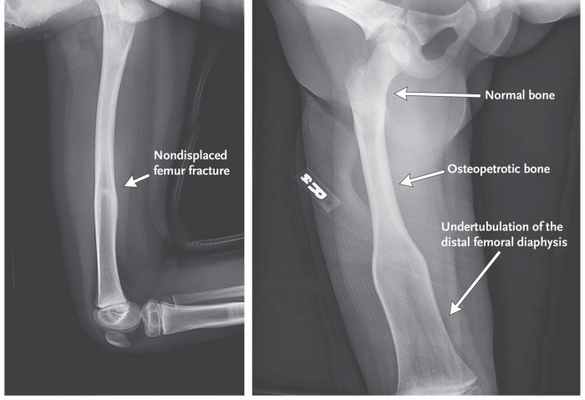

Проявления остеопетроза на рентгенологическом снимке